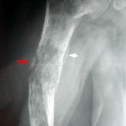

Aspect typique : Lésion métaphyso-diaphysaire, agressive, perméative, avec une compensante des parties molles de taille disproportionnée et avec une corticale osseuse relativement bien respectée.

Aspect Radiologique :

- aspect identique dans la forme primaire et dans la forme secondaire

* localisation diaphysaire ou métaphysaire

* " tumeur allongée dans la diaphyse "

- extension épiphysaire plus fréquente que les métastases et le myélome

- tumeur avec aspect moucheté (type 2 de Lodwick) ou perméatif (type 3 de Lodwick)

* lésion ostéolytique à limites floues 69%, mixte 31 %, rarement condensante pure

- appositions périostées de type spiculé ou lamellaire chez 50% des patients

- séquestres osseux 1/10

- extension au sein des parties molles. 48 %